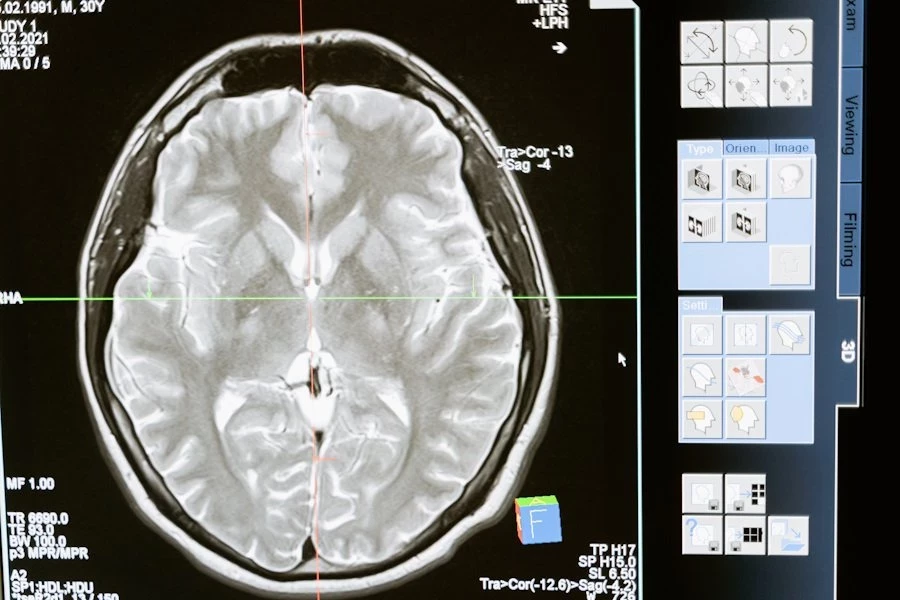

Зрительная рабочая память — это система мозга, которая помогает нам временно удерживать важные визуальные детали, например, при чтении, решении головоломок или сравнении объектов. Исследователи опирались на тета-гамма-модель, которая связывает объем рабочей памяти с частотой тета-колебаний мозга. Эти ритмичные волны появляются в переходе от бодрствования к расслаблению.